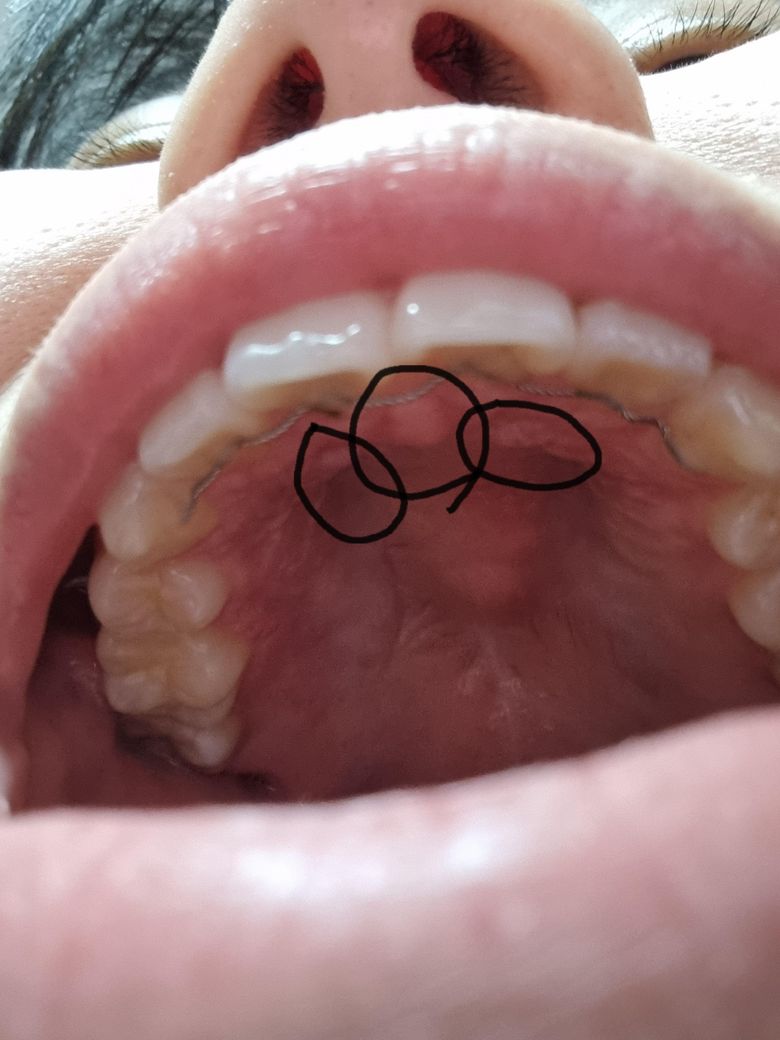

입천장이 구내염인지 맞는지 모르겠음 아시며답좀 부탁해요

입천장이 뜨거운물 먹을때 통증이있고 밥먹을때도 통증이 있는데 구내염이 맞는걸까요? 원인을 알고싶네요 동그라미친부분이 구내염이 맞는지 알고싶어요 닿기만 해도 통증이 생겨서 너무불편해요 구내염이 맞다면 구내염약을 먹으면 될까요?

구내염은 아니고 아래 치아가 입천장에 교합이 되거나 입천장에 뭔가 자극을 받아서 생긴거 같습니다.

구내염일 가능성이 높아보이나 구내염에는 특별한 약이 있지 않으며 시간이 지나면 좋아지게 됩니다. 염증완화를 위해 소독용 헥사메딘 가글액 사용 및 구내염연고 사용이 통증 및 염증개선에 도움이 됩니다.

네 통증이 있는 구내염으로 보입니다. 보통 1~2주면 자연적으로 호전되고 구내염 관련된 연고를 바르셔도 되겠습니다.